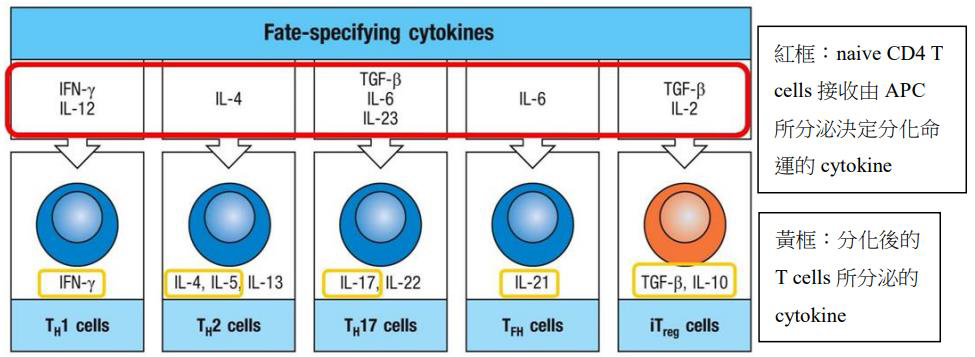

- 開始增殖並分化成不同亞型的效應 T 細胞(如 Th1、Th2、Th17、Treg)

- 只能選一條路走 (拮抗)

TH1

- 殺細菌

- IFN-γ,CD40/CD40L 活化 Macrophage → M1(吞噬特化)

TH2

- 寄生蟲 (嗜酸)

- M2 Macrophage 啟動修復

TH17

- 促進 neutrophils 產生

- IL-17

- 骨髓的基質細胞(stromal cell)和髓細胞(myeloid cell)產生G-CSF →嗜中性球(neutrophils)。

- IL-22

- 上皮細胞脫落及再生加速

- IL-17、IL-22 促進上皮細胞產生抗微生物蛋白(antimicrobial peptides)。

- 殺胞外細菌和真菌。

- 殺胞外細菌和真菌。

TFH

- B cell Isotype switch

- Cytokines 導致分化

- TGF-β → 抑制